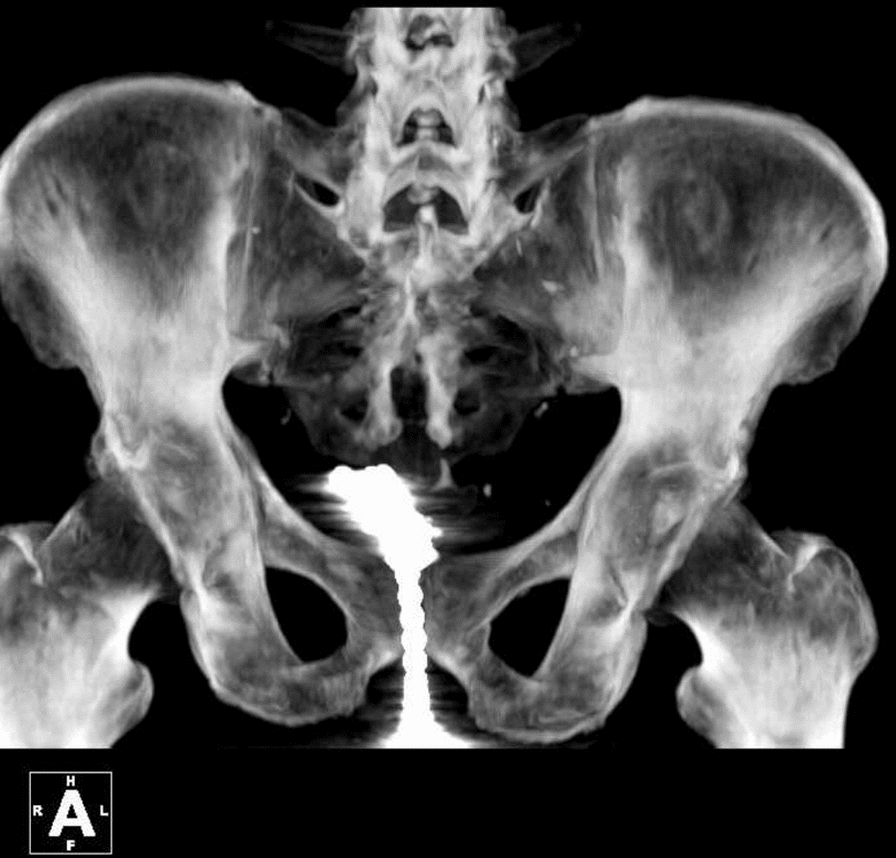

Case presentation: A 64 year-old Han male patient presented to the emergency department with urinary retention and dysuria. He had inserted magnetic beads into his urethra to relieve perineal discomfort caused by prior trauma. After being unable to remove the beads using his usual method, he sought medical assistance. A multidisciplinary approach involving urologists, psychologists, and acupuncturists was employed. The beads were successfully removed through endoscopic procedures and a suprapubic bladder incision. The patient also received acupuncture for pain relief and psychological counseling to address underlying motivations and develop healthier coping strategies.